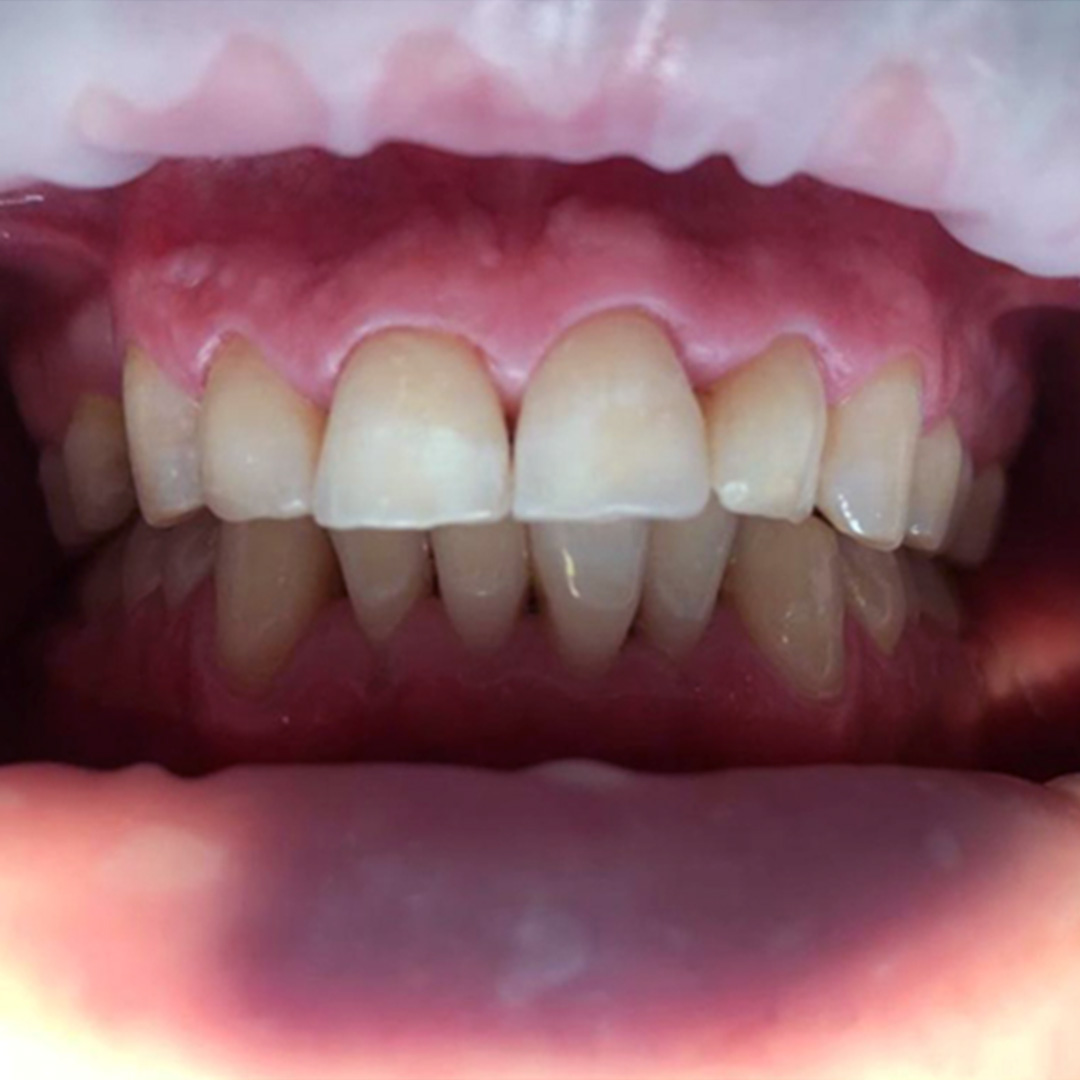

До и после лечения

В ходе процедуры Еленой Сергеевной были проведены следующие работы:

- анестезия;

- обработка и препарирование зуба;

- реставрация с использованием композитного материала.